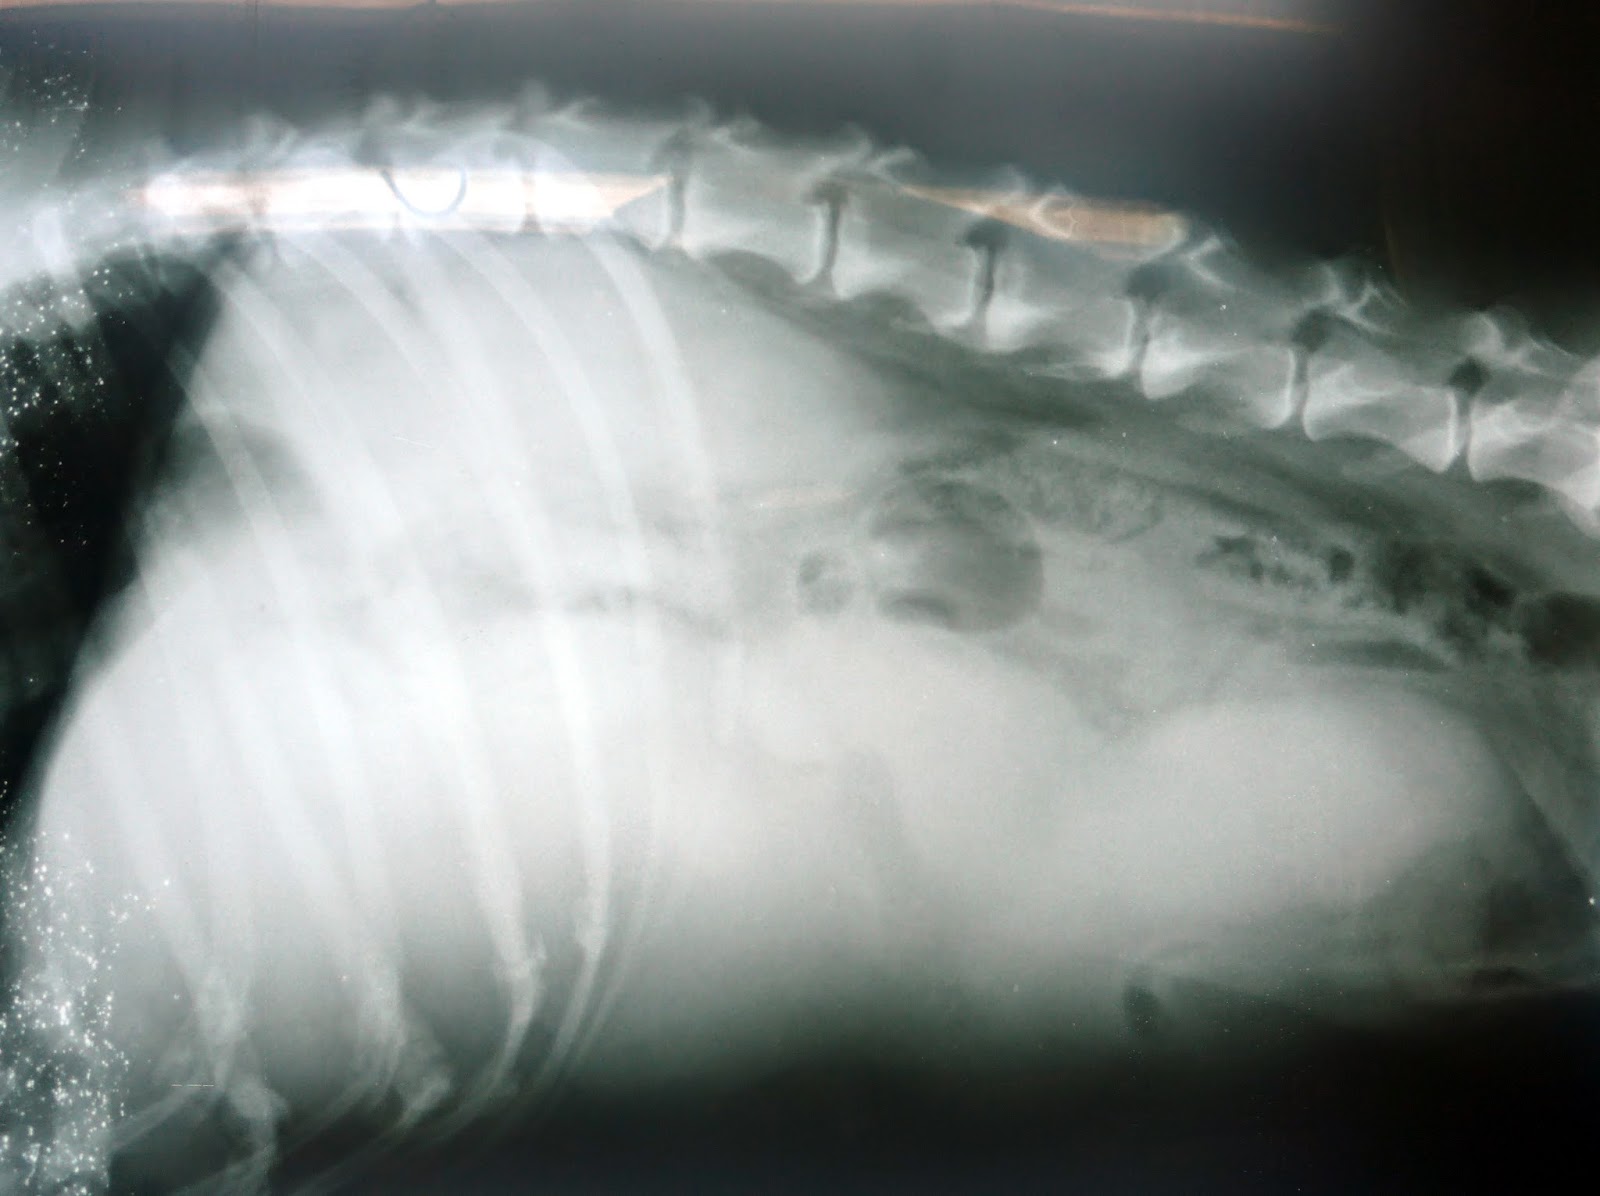

Tumor de bazo en perros

WebEl tumor de bazo es un tipo de cáncer que es común en perros y relativamente raro en los gatos y sus signos a menudo dependen de la localización del tumor, que van desde la. WebEn perros, del 0,3 al 2 por ciento de los tumores registrados se encuentran en las necropsias; el siete por ciento de todos los tumores son malignos; y alrededor del 50 por. WebCáncer de Bazo en perros. Al igual que los seres humanos, los perros y en general los animales domésticos pueden sufrir un sin número de enfermedades, entre. WebLos quistes sebáceos son un tipo de tumor benigno muy común en los perros. En pocas palabras, se producen por la acumulación de sebo, sustancia lipídica cuya función es. WebLas enfermedades más típicas que sufre el bazo son los tumores linfoma y hemangiosarcoma. El hemangiosarcoma es el tumor más frecuente en perros. Los. WebEl tumor de bazo es un tipo de cáncer que es común en perros y relativamente raro y sus signos a menudo dependen de la localización del tumor, que. WebSi es maligno ni que no reventar a terminará en metástasis y también, adiós perro. Si se opera hay mucho riesgo a que muera por su problema cardíaco, pero si sale bien y el.